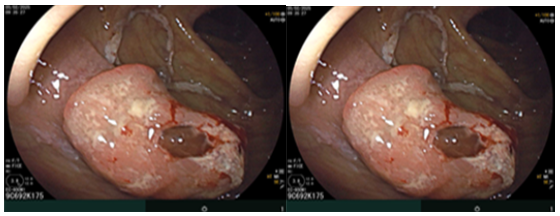

Đánh giá tổn thương trên phim chụp cộng hưởng từ: Nhu mô hạ phân thuỳ IV có ổ tổn thương dạng dịch, kích thước 38x52mm, trong có vài sỏi, sỏi lớn nhất kích thước ~27x37mm, có thông với nhánh đường mật gan phải lân cận, ngấm thuốc viền sau tiêm, chèn ép ngã ba đường mật, gây giãn đường mật trong gan hai bên

Hình 2. Hình ảnh giãn khu trú đường mật gan trái, tạo cấu trúc dạng nang và sỏi đường mật bên trong( vòng tròn đỏ), chèn ép kèm giãn đường mật trong gan hai bên trên phim chụp MRI